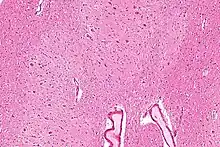

The dentate nucleus is a cluster of neurons, or nerve cells, in the central nervous system that has a dentate – tooth-like or serrated – edge. It is located within the deep white matter of each cerebellar hemisphere, and it is the largest single structure linking the cerebellum to the rest of the brain.[1] It is the largest and most lateral, or farthest from the midline, of the four pairs of deep cerebellar nuclei, the others being the globose and emboliform nuclei, which together are referred to as the interposed nucleus, and the fastigial nucleus. The dentate nucleus is responsible for the planning, initiation and control of voluntary movements. The dorsal region of the dentate nucleus contains output channels involved in motor function, which is the movement of skeletal muscle, while the ventral region contains output channels involved in nonmotor function, such as conscious thought and visuospatial function.

Location

The architecture of cerebellum has a form that resembles the structure of a crystal, so a slice anywhere in the cerebellum gives repeated architecture. The eight cerebellar nuclei, located within the deep white matter of each cerebellar hemisphere, are grouped into pairs, with one of each pair in each of the two hemispheres. As a chunk of tissue, the dentate nucleus with overlying cerebellar cortex makes up a functional unit called the cerebrocerebellum. Thus, there is a part of cerebellum that communicates exclusively with the dentate nucleus.[4]